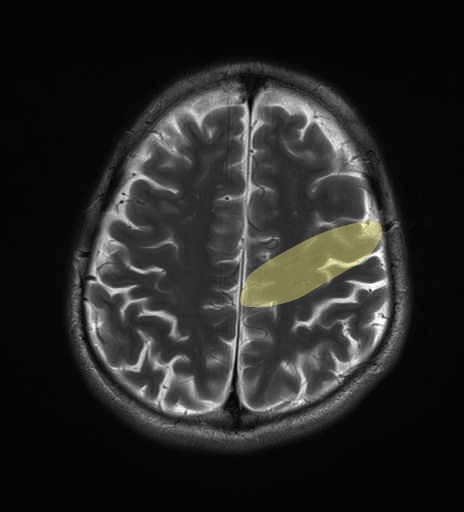

運動系 錐体路系に色を付けました。

■皮質脊髄路(いわゆる錐体路):一次運動野から脊髄遠隔の下位運動ニューロン細胞体まで